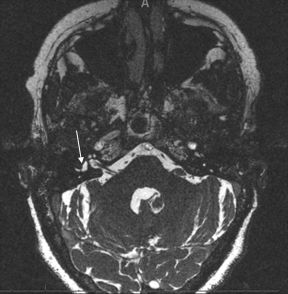

Partially thrombosed aneurysm...

#neuroscience#neurorad pic.twitter.com/5D9icRAojv -